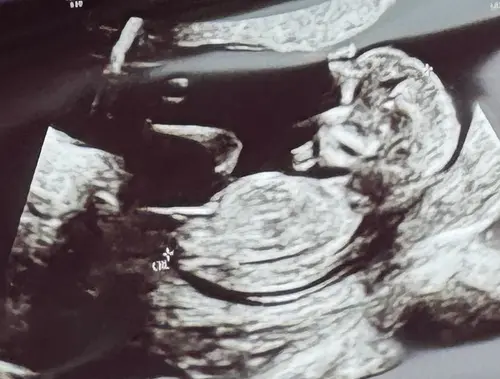

Wat denken jullie? Echo op 12w5d.

Ik denk een meisje 😊